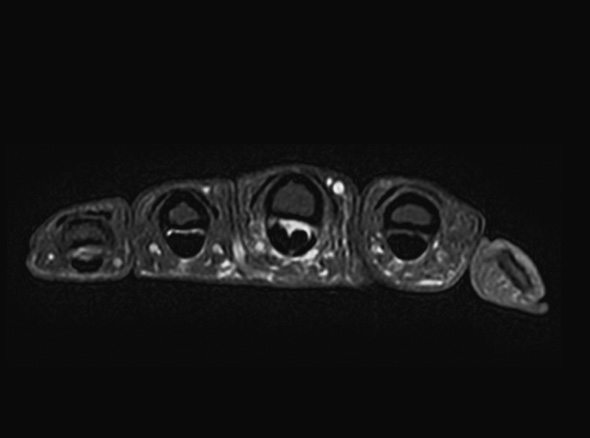

학술적으로는 협착성 굴곡건염이라고 표현하고, A1 활차라는 터널에 굽히는 힘줄이 마찰되다가 힘줄의 내부적인

변화가 일어나 병이 생긴 상태를 의미합니다. 내부적인 변화가 심해질 경우 힘줄이 부어 결절을 이룰 수도 있는데

이러한 경우 A1 활차에 끼어서 딸깍 거리거나 걸려서 안 펴지는 증상이 생깁니다.

손가락을 굽히거나 펼 때 통증이 있고 A1 활차에

해당하는 부위를 눌렀을 때 심한 통증이 발생